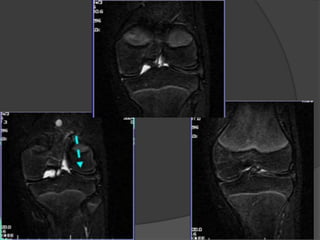

Contusiones óseas

 Son microfracturas

trabeculares, sin fractura

cortical, pero con edema e

hiperemia medular

 RM:

 áreas mal definidas de

alteración de señal en la

médula ósea de

comportamiento hipointenso

en T1 e hiperintenso en T2

(dura 6-12 semanas)